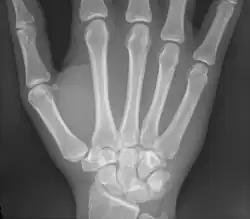

Os humain de la main